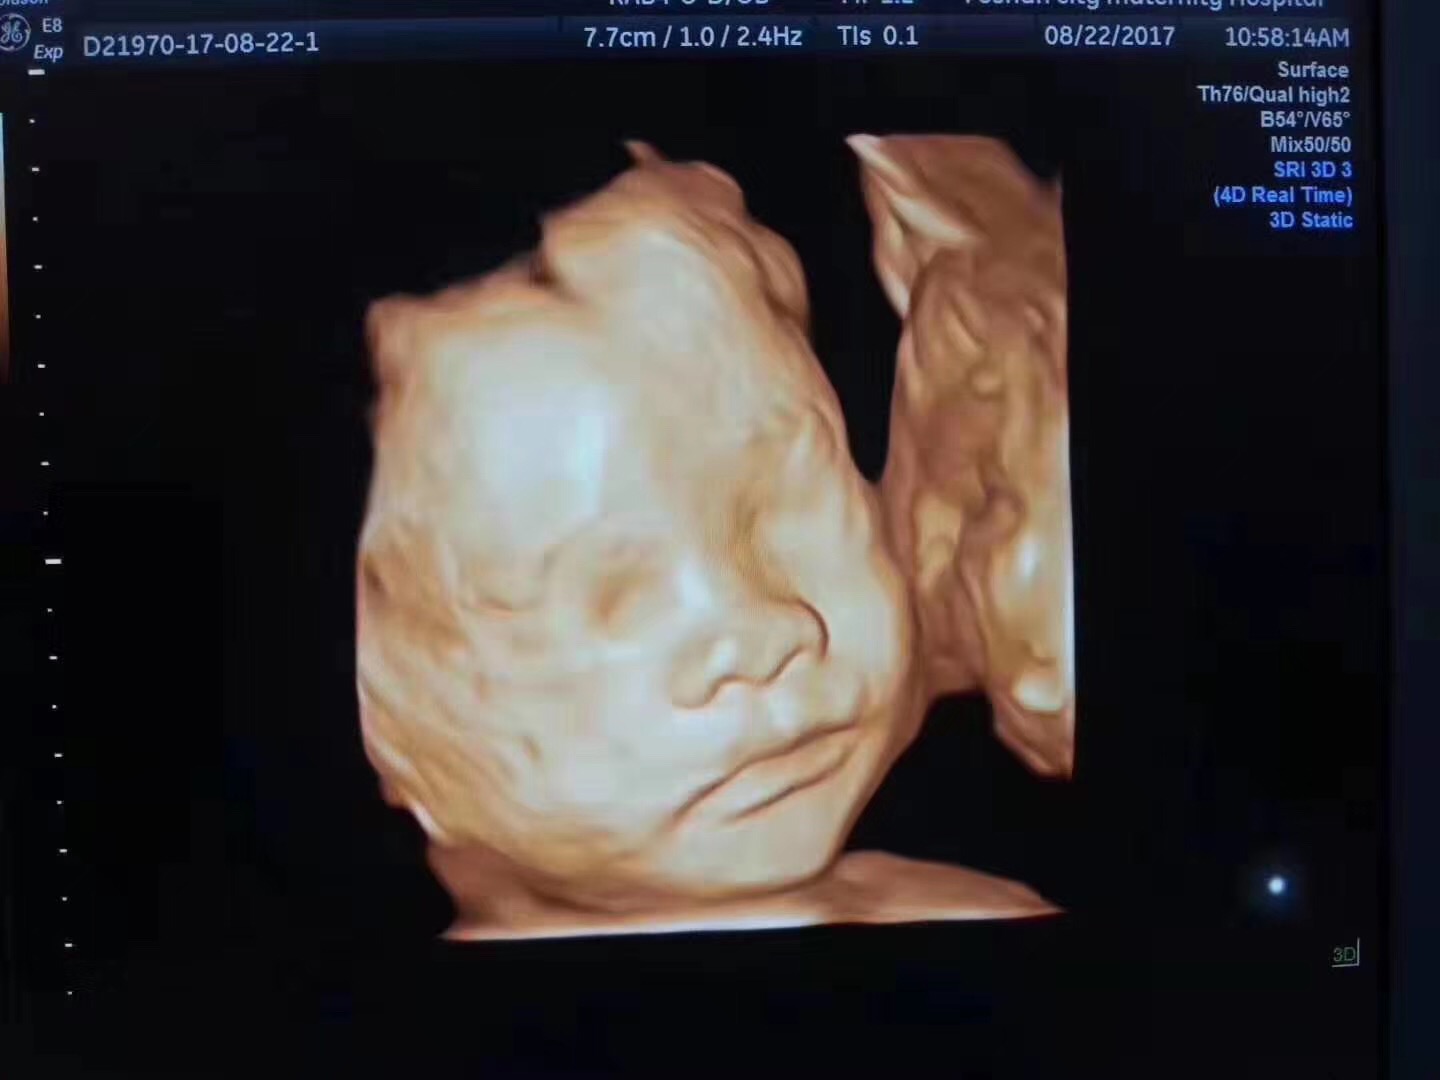

4.超声影像(四维彩超)

微信图片_20191009094020.jpg

超声影像(四维彩超)可以对胎儿的发育状况进行比较全面的检查。

单胎为孕22-26周,双胎为孕20-24周。